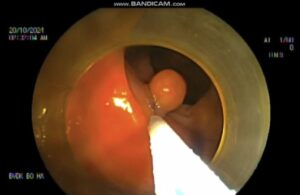

Vừa qua, Bệnh viện Đa khoa Bố Hạ ghi nhận nhiều trường hợp bệnh nhân đi khám sức khỏe định kỳ, quá trình nội soi đại tràng phát hiện nhiều polyp với kích thước lớn.

Nội soi đại tràng là một trong những biện pháp hiệu quả nhất để phát hiện chính xác polyp đại tràng.